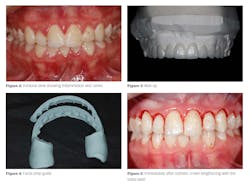

At the first appointment, a full-mouth series of radiographs, photographs, and dental records were obtained. Impressions were taken for a diagnostic wax-up, and the patient assisted in selecting the shape of her teeth (figure 3). I recommended making a preparation guide from the wax-up as this greatly assists the clinician while the teeth are prepared (figure 4). The preparation guide assures the clinician that adequate tooth structure is removed.

Because the size of the teeth is one of the most noticeable factors in a smile, it is important that the teeth look proportional and have an ideal width-to-height ratio.The patient was sent to the periodontal specialist, who used a 9.3-micron CO2 Solea laser (Convergent Dental) in a minimally invasive closed-flap esthetic crown lengthening procedure. No sutures were needed, and total chair time took less than 30 minutes to achieve the desired gingival height and shape (figure 5).

One week later, the patient returned to the office for a post-op check, and any necessary bite adjustments and/or esthetic recontouring were performed. Final photographs were taken and before-and-after photos were evaluated (figures 6–8).